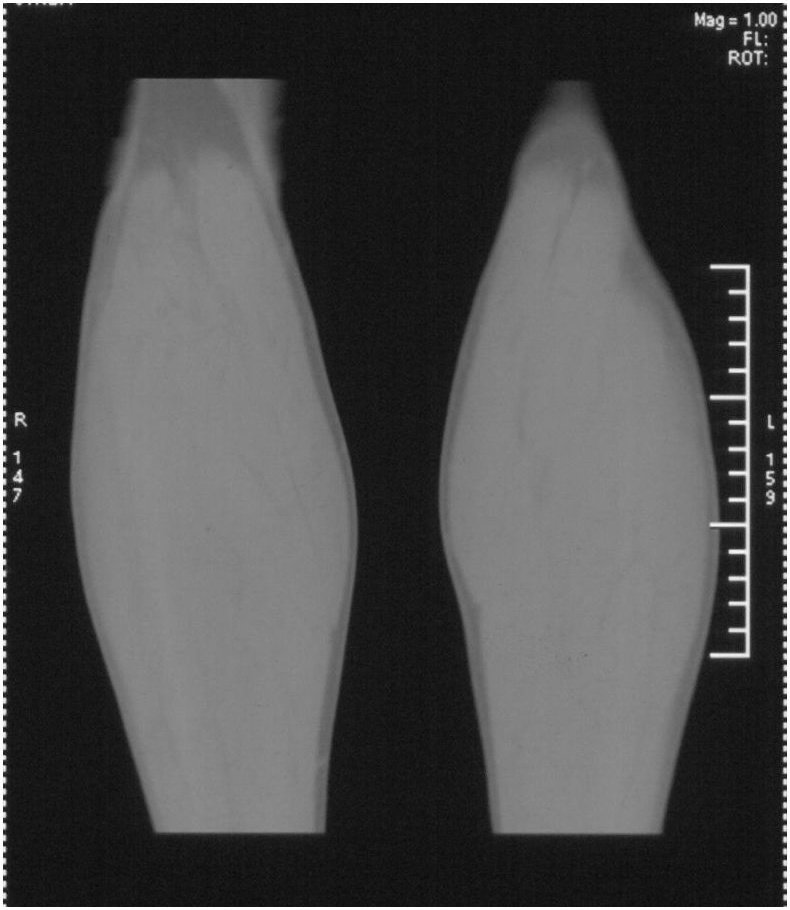

男,42岁。4个月前钢筋钝伤右侧小腿部,当时因无明显外伤,未引起重视。一周后因受伤腿部疼痛,发现肿胀,随后到当地医院进行检查(2008年4月16日)。因未发现骨质异常未引起重视,仅仅进行口服抗生素治疗处理。经过一段时间治疗但未见明显治疗效果在5月29日又进行x线检查,发现有胫骨密度上段密度增高,又进行抗炎治疗,仍未见效果。又在7月3日进行x线检查,仍然报告有胫骨上端密度增高,并建议ct检查。以下是相关检查结果:

髓腔密度呈絮状增高,胫骨上端内侧可见层状骨膜反应,考虑骨髓炎.

髓腔密度呈絮状增高,胫骨上端内侧可见层状骨膜反应,肌间隙模糊,考虑骨髓炎.

该患者到某三级医院进行会诊,并重新作了平片检查,认为畸形性行骨炎: